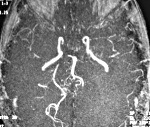

• Церебральная ангиография. Может осуществляться рентгенологически и при помощи МРТ сосудов. По различным данным, выявить сосудистые изменения удаётся у 40-90% больных. На ангиограммах отмечается смазанность сосудистого контура, сужения, участки дилятации, прерывание, окклюзия, наличие множественных коллатералей.